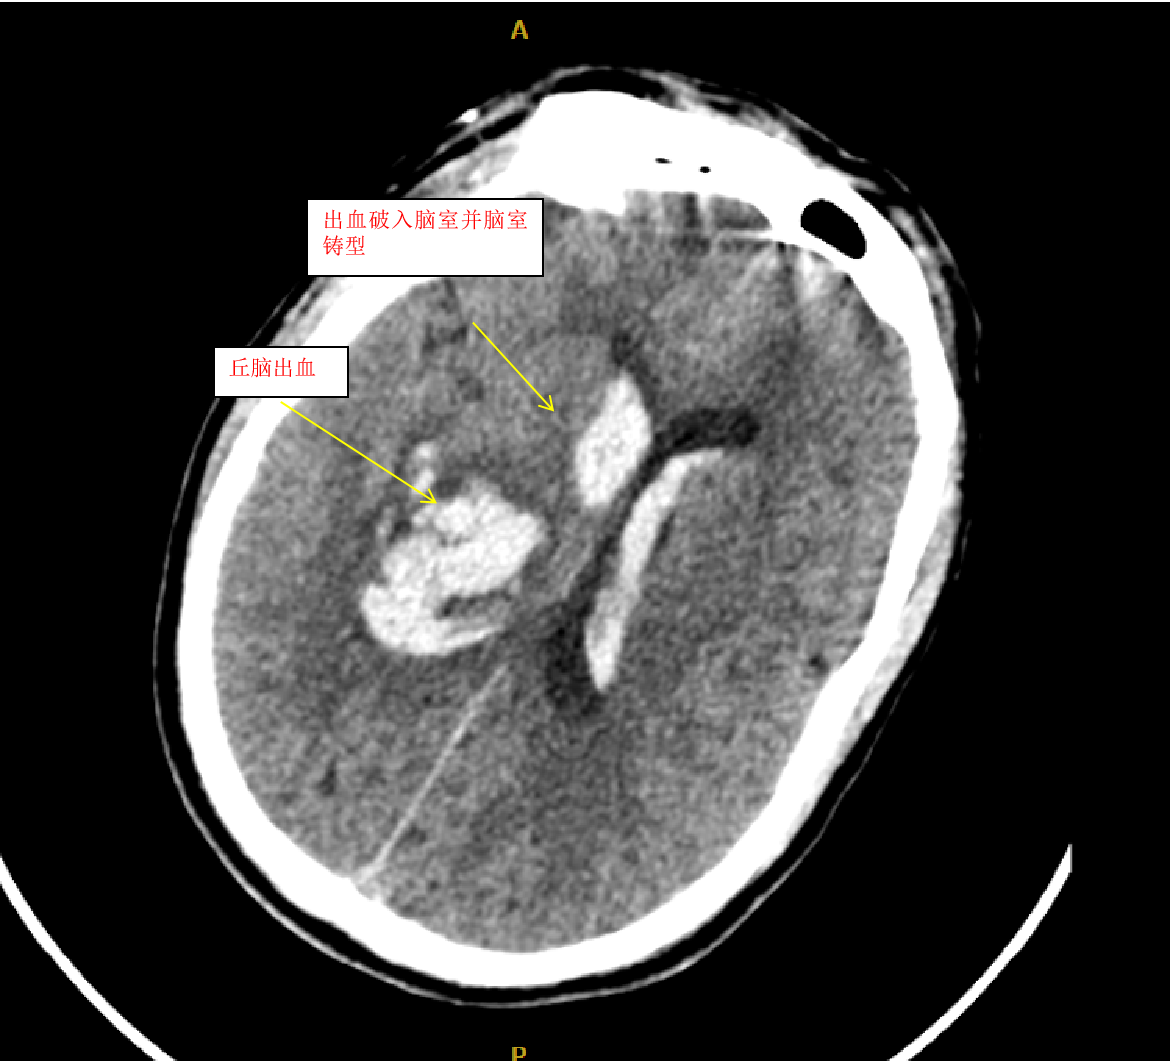

患者田某某,男,62岁,因突发昏迷不醒2小时而收入县医院神经外二科,经颅脑CT检查,诊断右侧丘脑出血并大量破入脑室,脑室铸型。病人入院时处于深度昏迷状态,四肢强直,这种病人病情往往很重,死亡率极高,致残率更高,从以往的经验来看,这种病人很少能抢救成功。

我们收到此病人后,立即给予术前准备,并在局麻下行双侧脑室外引流术,由于病人脑室有大量出血,穿刺置管有很大的技巧,因为大量的脑室出血,致脑室铸型,打乱了正常的解剖结构,穿刺失败的可能性很大。经术后复查颅脑CT,发现右侧管道引流较通畅,决定拔除左侧引流管,并通过右侧引流管给予尿激酶注入反复溶解血块并引流出血性液体,共应用尿激酶10次,每日一次,为了预防感染,并在每次冲洗时给予严格换药。于第10天经复查颅脑CT发现脑室出血已基本清除,决定给予拔除脑室引流管。为了放出残留血性脑脊液,尽量廓清病人脑脊液,于拔管后第二天开始给予腰穿,共进行腰穿10次,每日一次,腰穿时尽量多放出脑脊液,才能取得更好的效果。于近日复查颅脑CT发现丘脑出血已完全吸收,脑室积血已完全清除,未出现脑积水,未出现颅内感染。经过这段时间的治疗后病人的意识状况已明显好转,由深昏迷转为神志恍惚,肢体的偏瘫也逐渐好转,目前仍给予肢体康复训练治疗,几天后就能治愈出院。